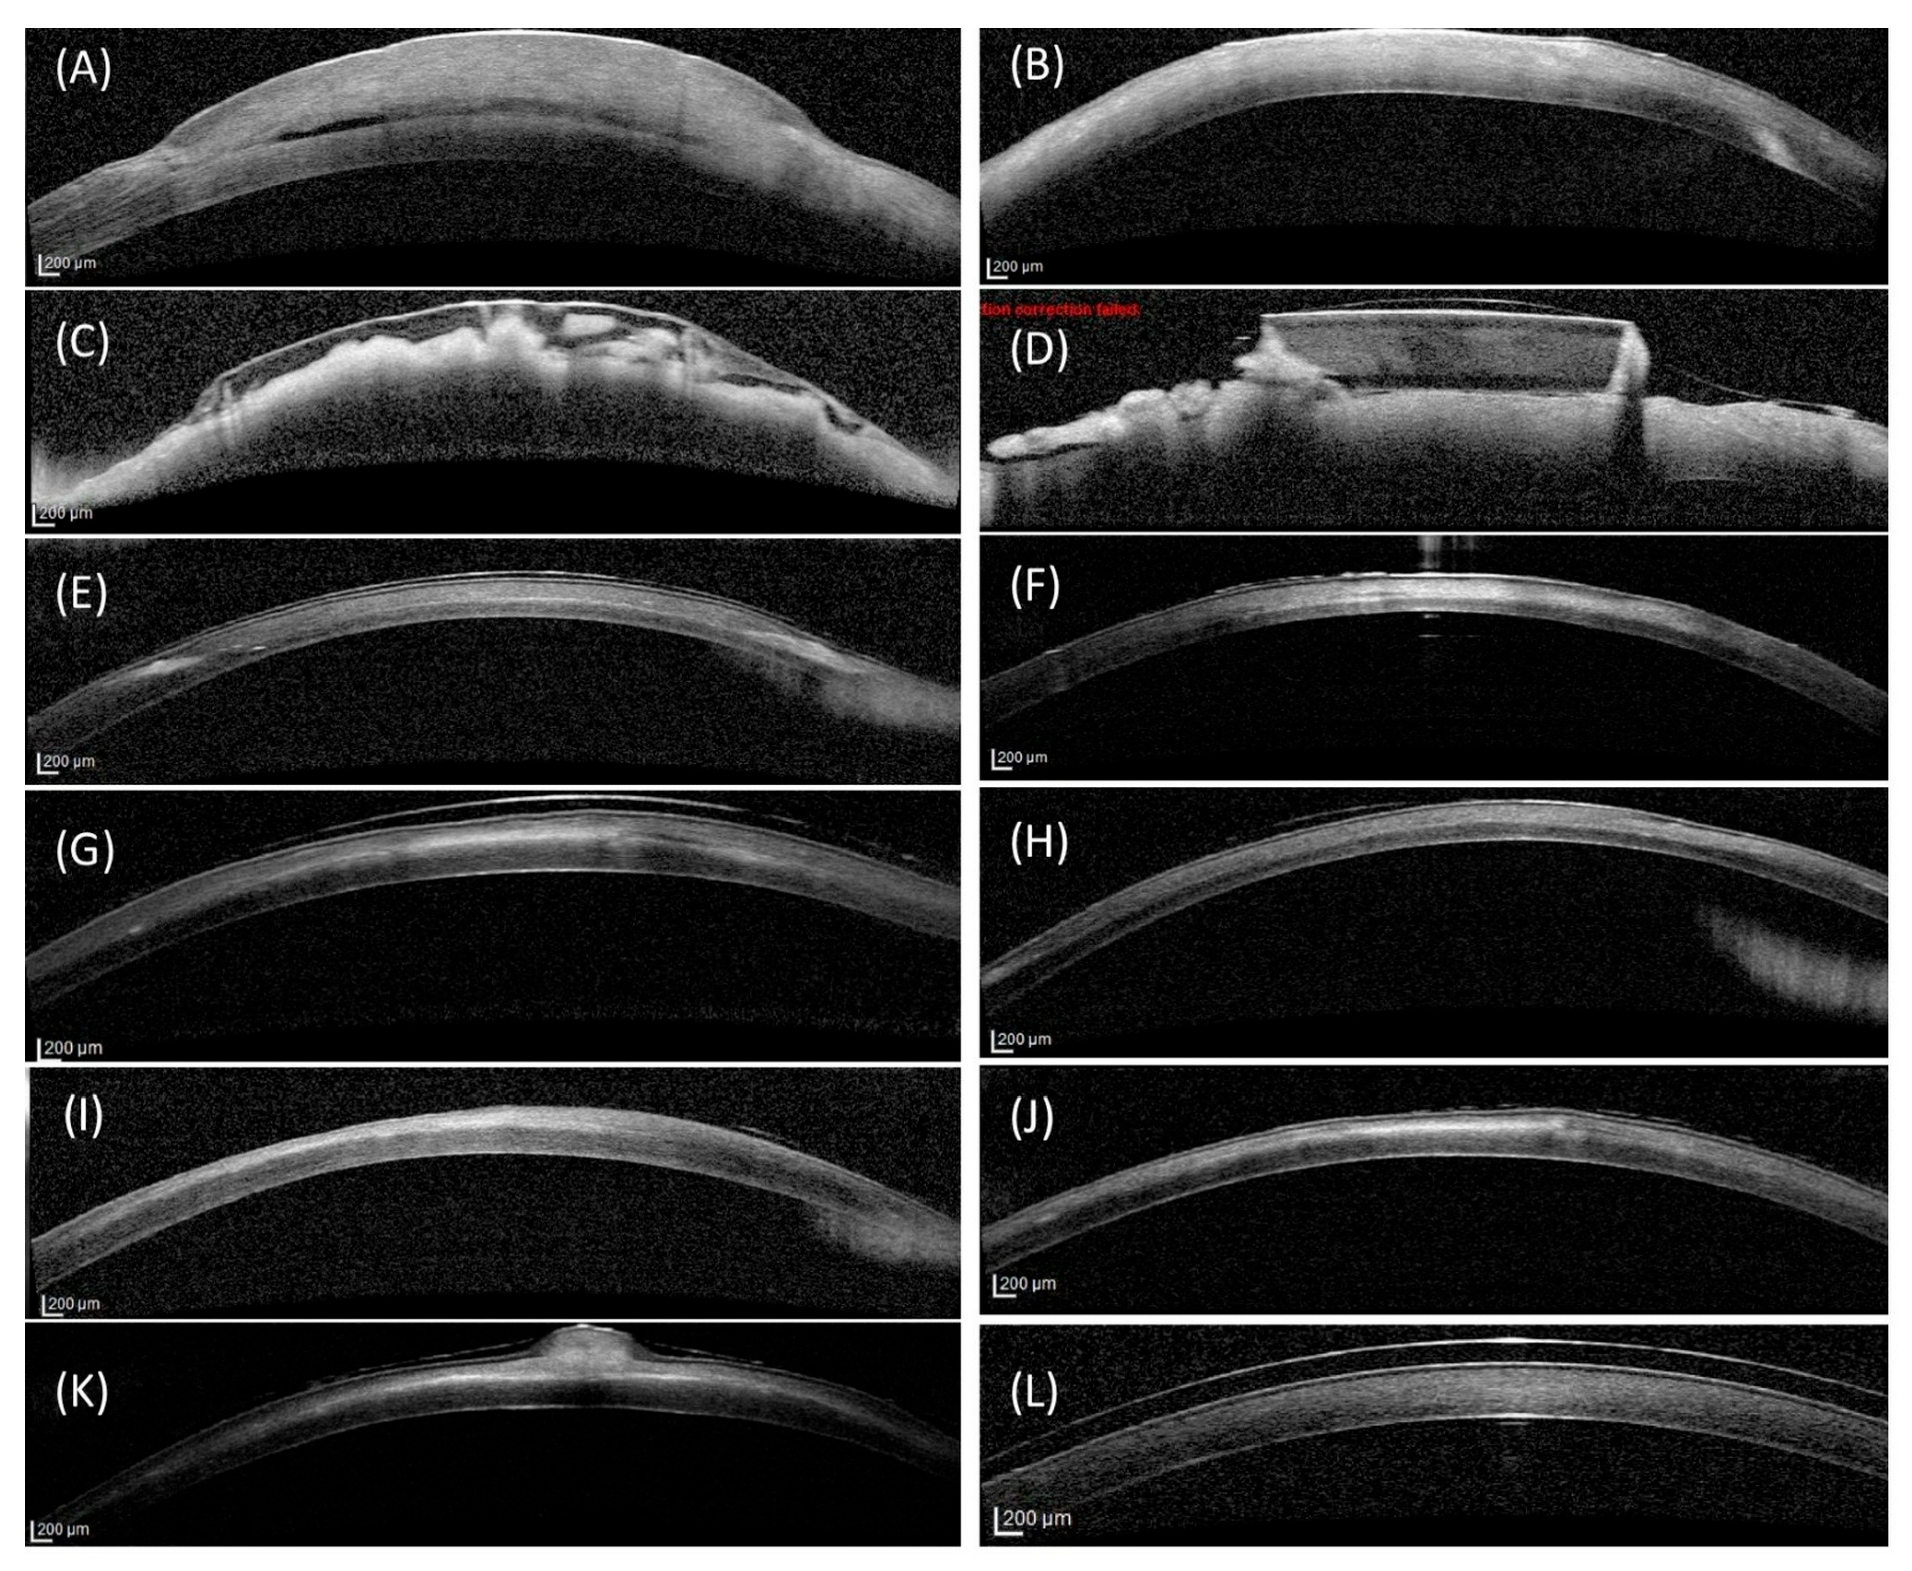

3.3. Optical Coherence Tomography